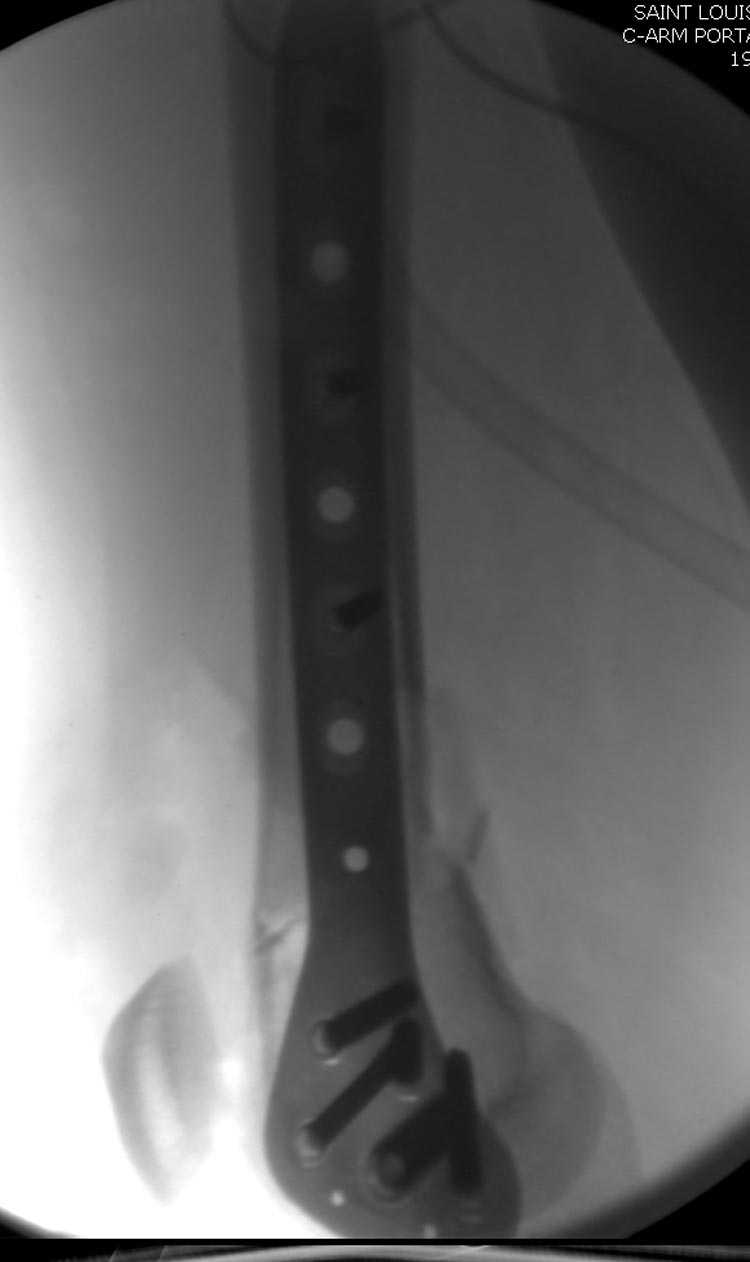

[Ortho] Дистальный перелом бедра

Почти все компании имеют пластины с угловой стабильностью, начиная от Stryker, Zimmer NCB и DePuy Polyaxial Plate . Если у NCB шуруп блокируется специальной шайбой, то Polyaxial Plate имеет вариабельный угол введения шурупов.

Поэтому такие меж и над- мыщелковые переломы более предпочтительным считается фиксировать мыщелковыми пластинами

Устанавливается из малого разреза "не вскрывая сустав" со стороны латерального мыщелка, и Insertion Jig позволяет установить пластину "мостовидно" перкутанно в проксимальном отделе, "не вскрывая и не трогая" место перелома.

Имя     : distal femur crm 6.jpg